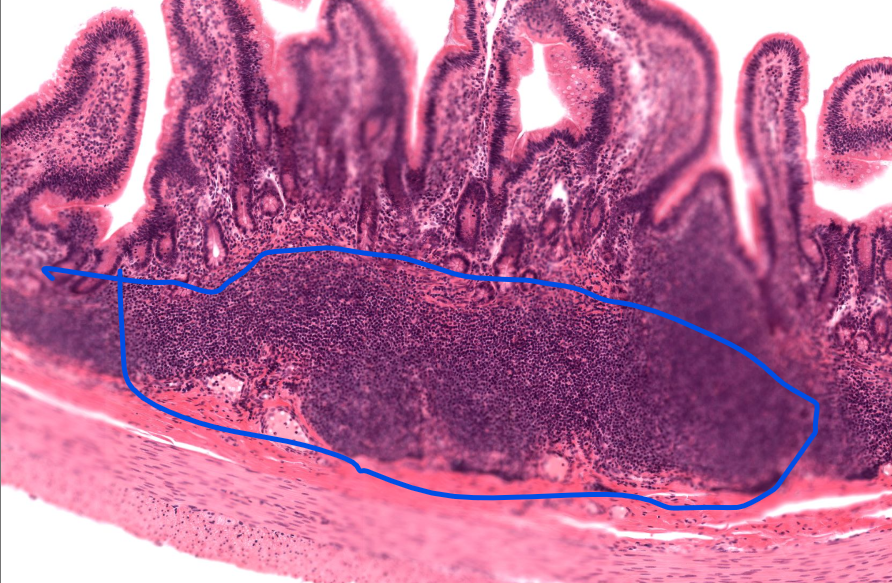

notice the immune tissue in the submucosa (peyers patches)

peyer’s patch

cluster of lymphocytes in the ilium